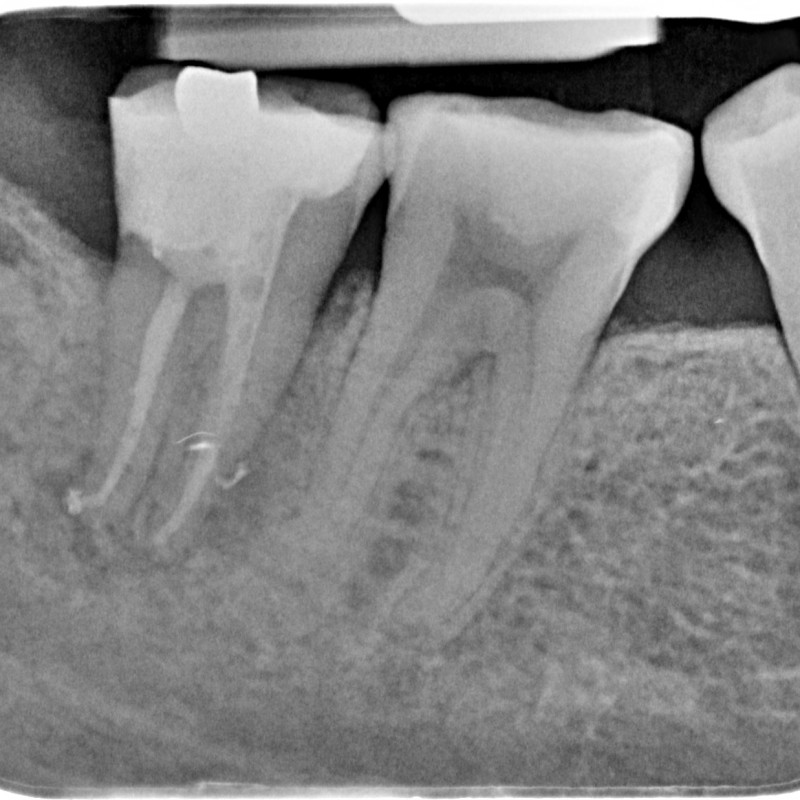

890205-14-5252-X-20150430-150718-XSYHD7J+NTN8-4